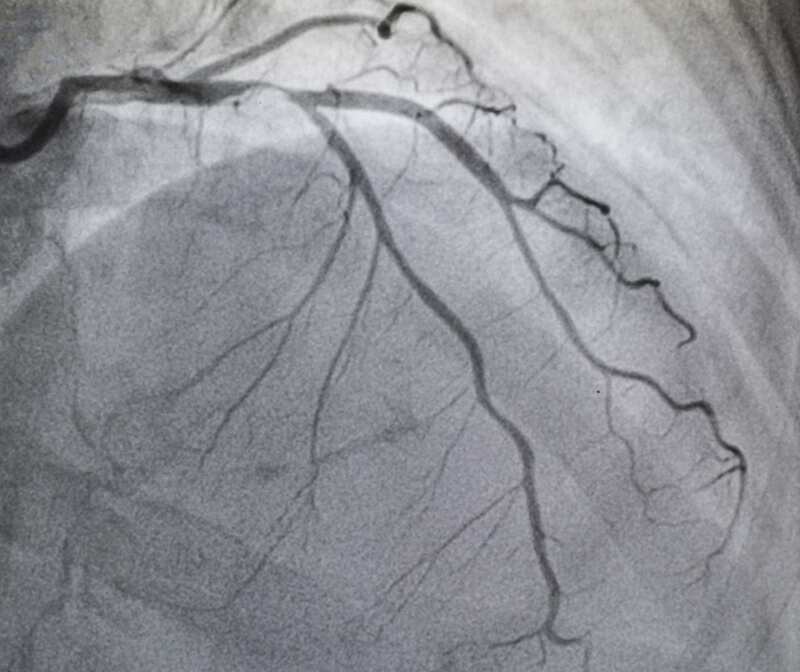

رگهایی كه به عضله قلب شما خون می­رسانند را عروق كرونر می­گویند. این رگها ممكن است توسط جسمی به نام پلاك .....

سی تی آنژیوگرافی میتواند اطلاعات جامع و كاربردی در زمینه آناتومی عروق، وجود ناهنجاری های مادرزادی عروقی و نحوه درگیری رگ مبتلا ...

توانایی تشخیص سی تی آنژیو با سایر روشهای تشخیص غیر تهاجمی در قلب و عروق...